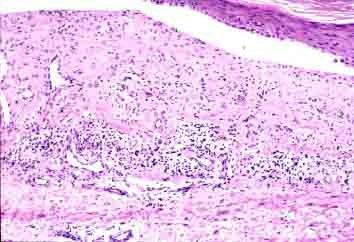

此新闻报道的出现,引来了人们对血小板减少性紫癜的关注热潮。而针对血小板减少性紫癜的发生,邯郸燕赵中医医院血液科医师冀兆魁表示,血小板减少性紫癜,是一种以血小板减少为特征的出血性疾病,主要表现为皮肤及脏器的出血性倾向以及血小板显著减少,可分为特发性、继发性和血栓性血小板减少性紫癜。发病初期患儿腿部常常会出现一块一块的乌青,皮肤上还会出现小血点。此时,家长若发现孩子皮肤经常出现乌青块,特别是四肢部位,如果不是因为明显摔伤或碰伤导致,那就需要注意了,一定要及时把孩子送到医院进行进一步的检查诊断。

3、慢性 慢性血小板减少性紫癜早期表现不明显,占血小板减少性紫癜的一半以上,女性高于男性,在20-50岁多发。病人会出现持续性出血,甚至反复发作,局部出血,如鼻衄、口腔。瘀点、瘀斑可发生在全身皮肤与粘膜,多发生在四肢远端,也会出现消化道和泌尿道出血。

4、特发性 对于血小板减少性紫癜病人的症状需要大家了解,皮肤有出血、瘀点症状表现,也有患者出现轻度肝脾肿大。出血严重,以皮肤、粘膜自发性出血最多见,常常为皮肤、粘膜、牙龈、眼结膜和鼻腔多见,胃肠道、泌尿道出血少见,严重的情况下有颅内出血的表现。病前有病毒感染史,例如上呼吸道感染、麻疹、水痘等。